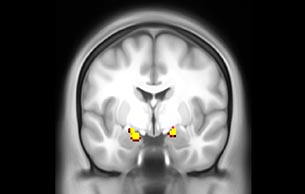

Emotional n-back task combines a test of working memory with the use of emotive (faces) and neutral (places) images. The contrast in the images is between the activity when faces are presented compared to places, showing activation in the amygdala, fusiform, and occipital face areas.

Processing based on the Human Connectome Project (HCP) pipelines. The high resolution of the fMRI data allows extraction of the cortical surface, with minimal averaging of non-cortical signal. Surface based analysis provides improved cross-subject alignment, and prevents signal contamination between adjacent sulci.

Group analysis of 88 9- and 10-year olds part of ABCD, all scanned at UVM on Philips Achieva 3.0T dStream. Scale runs from red p=0.001 to yellow p<10ˆ-5. Images provided by Dr. Watts.

Acquisition using the ABCD protocol for fMRI with TR 800 ms, TE 30 ms, flip angle 52°, 2.4 mm isotropic imaging resolution with a 216×216×144 mm3 field of view using a MultiBand acceleration factor of 6 (60 slices, no gap). Two runs of 5 minutes per subject.